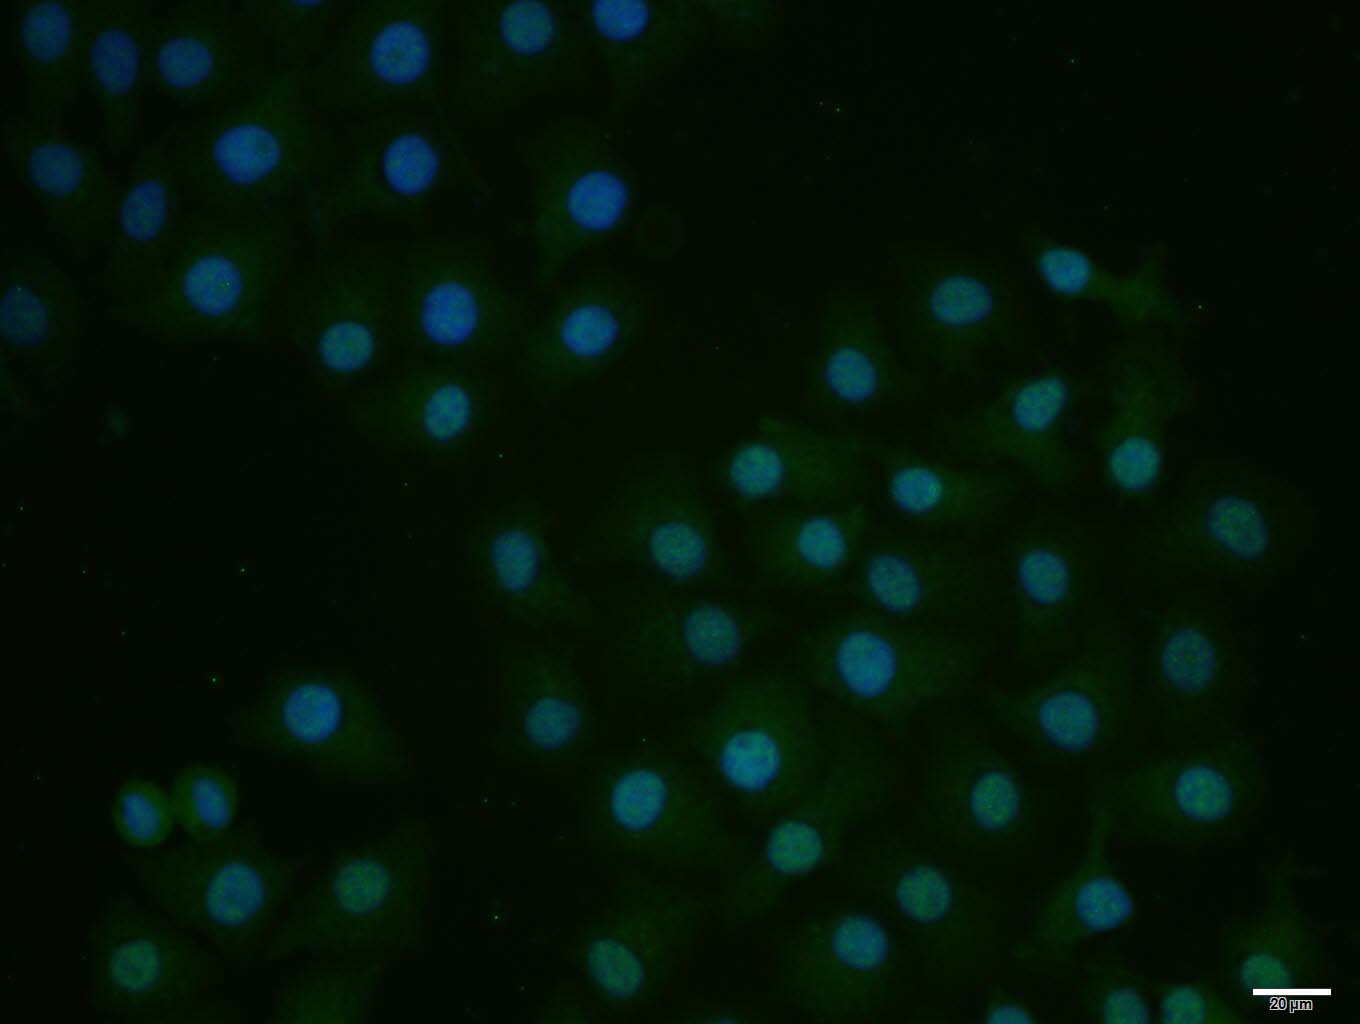

HepG2 cell; 4% Paraformaldehyde-fixed; Triton X-100 at room temperature for 20 min; Blocking buffer (normal goat serum, C-0005) at 37°C for 20 min; Antibody incubation with (E2F1) polyclonal Antibody, Unconjugated (bs-23185R) 1:100, 90 minutes at 37°C; followed by a conjugated Goat Anti-Rabbit IgG antibody at 37°C for 90 minutes, DAPI (blue, C02-04002) was used to stain the cell nuclei.